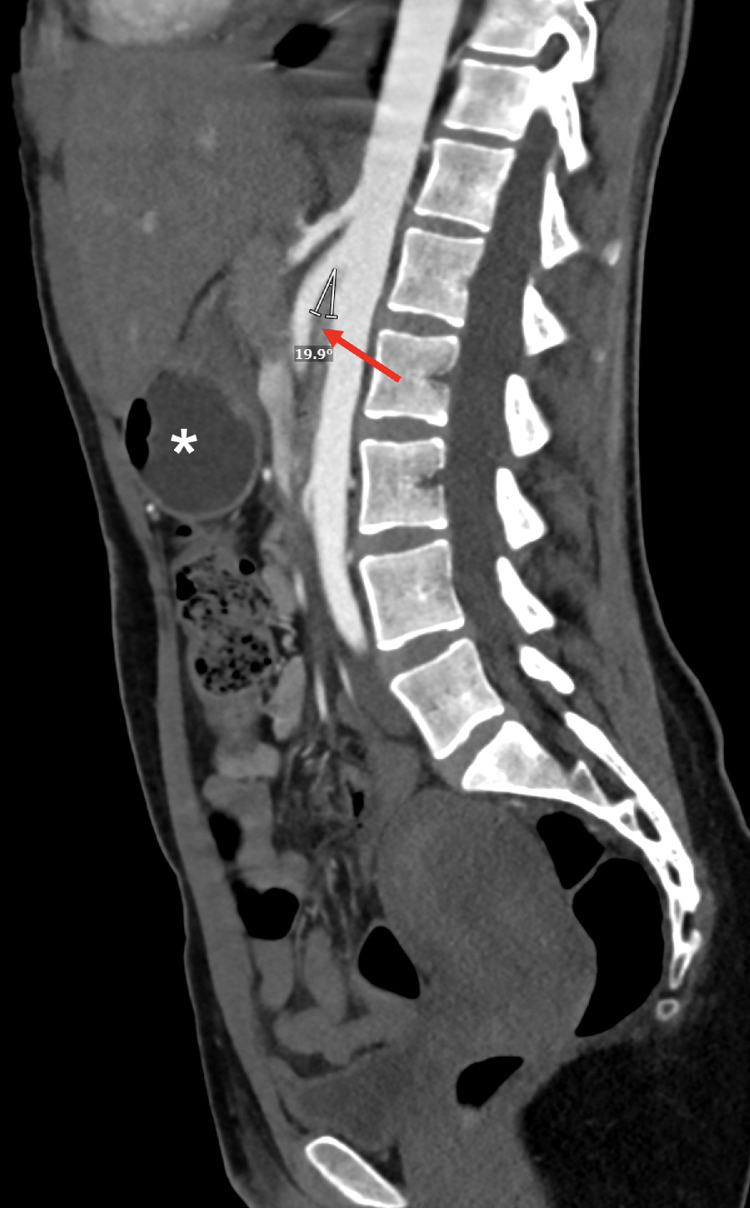

Fig. 2.

CT angiography of the abdomen and pelvis, sagittal slice, revealing decreased aortomesenteric angle of 19.9 degrees (measured), and narrowing of the second portion of the duodenum (red arrow) at the junction of the superior mesenteric artery and aorta, as well as distension of the stomach (asterisk), suggestive of superior mesenteric artery syndrome.

A 24-year-old woman presented to the emergency room in the context of nausea, vomiting, and abdominal pain of 2 days duration. She had recently given birth and was discharged following an uncomplicated delivery and post-partum course 2 weeks prior to presentation. She endorsed ongoing substance use of opiates and cannabinoids. She denied fevers, chills, lightheadedness, dizziness, palpitations, melena, or hematochezia. Medical history was remarkable for seizure disorder managed with oral levetiracetam, which she was unable to take for several days owing to her current symptoms. She had a witnessed seizure after her initial presentation to the hospital for which she received intravenous levetiracetam. At the time of presentation, she was hypertensive (181/108 mm Hg) with otherwise preserved vital signs, and BMI was 21.08 kg/m2. On examination, she was thin, ill-appearing, with decreased skin turgor, and tenderness in the epigastric and suprapubic regions. Bowel sounds were present on auscultation and there was no rebound tenderness or guarding. Initial laboratory diagnostics revealed leukocytosis (11.5 k/uL; reference range: 4.0-10.8 k/uL) and hypokalemia (3.1 mmol/L; reference range: 3.4-4.5 mmol/L). Urinalysis was remarkable for proteinuria, hematuria, pyuria with bacteria, and trace leukocyte esterase. Molecular testing for COVID-19 was negative. A contrast enhanced computed tomography (CT) scan of the abdomen and pelvis revealed diffuse wall thickening of the gastric pylorus, narrowing of the duodenum at the junction with the SMA and aorta, dilation of the first part of the duodenum, decreased aortomesenteric distance of 6 mm (Fig. 1) and decreased aortomesenteric angle of 19.9 degrees (Fig. 2). She was admitted for further management of her symptoms, attributed to SMA syndrome, urinary tract infection, dehydration, electrolyte abnormalities, and the noted seizure. She was managed conservatively for her abdominal symptomatology; upon resolution of her nausea and abdominal discomfort, she was initiated on a clear liquid diet and oral medications with dietary advancement. Electrolyte abnormalities were corrected with intravenous and oral electrolyte replacement therapy. She was eventually transitioned back to oral levetiracetam at her usual home dose. She was discharged from the hospital with planned outpatient follow-up with gastroenterology.

SMA syndrome is a rare clinical entity, and risk factors include rapid weight loss, malignancy, malabsorption, cachexia, trauma, rating disorders, burns, and mechanical/structural variations (congenitally short or hypertrophic ligament of Treitz, duodenal malrotation, Ladd's bands, and lumbar hyperlordosis), with a noted female predisposition [4,5]. Our patient had several of these risk factors including female sex, pregnancy associated lordosis and post-partum weight loss. Her symptoms were classic - nausea, vomiting, and abdominal pain. CT scan showed an aortomesenteric distance of 6 mm (normal: 10-34 mm) and aortomesenteric angle of 19.9 degrees (normal: 28-65 degrees) along with a narrowed duodenal junction; the latter is due to the loss of mesenteric fat pad resulting in a decrease in the angle and reduced distance between the aorta and SMA leading to duodenal compression [2,6].